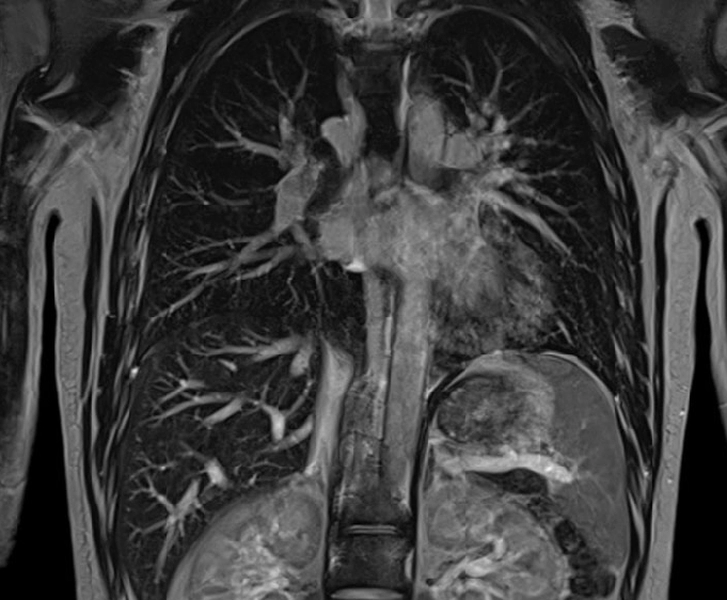

МРТ грудной клетки

МРТ органов грудной клетки – оптимальный метод для выявления патологических изменений в плевральной полости, трахее, легких, перикарде и сердечной мышце, межпозвоночных дисках и спинном мозге, диафрагме, лимфоузлах, сосудах лимфотока и кровотока.

Исследование обычно назначают для уточнения и дополнения данных, полученных с использованием других диагностических методов – рентгенографии, КТ, УЗДГ. Из-за наполненности воздухом сканирование легочной паренхимы не отличается высокой эффективностью, но для других органов, расположенных в пределах грудной клетки, оно подходит как нельзя лучше.